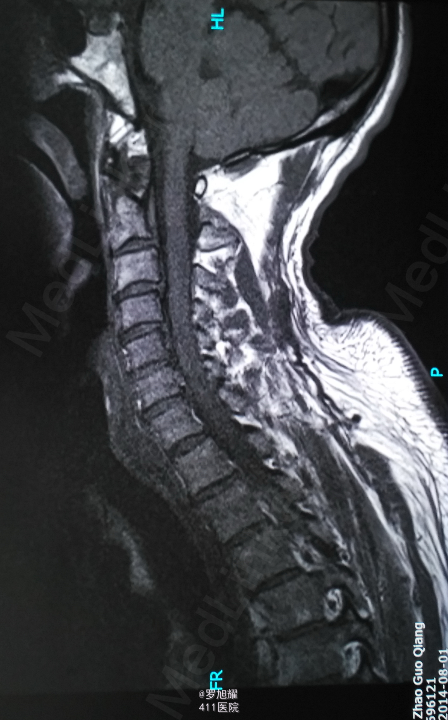

左侧锁骨平面以下痛温觉、位置觉消失,右半身感觉正常。会阴部感觉存在。左侧肢体肌力正常,右侧上下肢肌力0级。右侧腱反射均消失。影像学检查示双侧枢椎椎弓骨折,MRI脂肪抑制成像颈1-2平面脊髓信号略高。

入院立即给与大剂量甲强龙冲击治疗,辅以甘露醇脱水消肿,兰索拉唑保护胃黏膜,腺苷钴胺恩经复营养神经,伤后10天复查MRI脊髓信号增高明显,两周后生命体征稳定,肢体感觉和肌力见部分恢复,行颈2椎弓根螺钉、颈3侧块钉内固定术,因神经压迫不明显未行椎板切除减压。 术后3月骨折线基本消失,患者感觉肌力几乎完全正常,右肩残留疼痛磁共振检查发现肩袖损伤,暂予局封治疗症状缓解。

该患者术后4月随访瘫痪症状完全消失,感觉正常,右侧肌力已经接近5级,但Mri随访T2加权像仍可见明显的脊髓高信号,但是影像学上脊髓变性和患者的症状没有明显的相关性,说明神经功能的代偿潜能还是非常巨大的,各位老师和同仁是否同意呢?